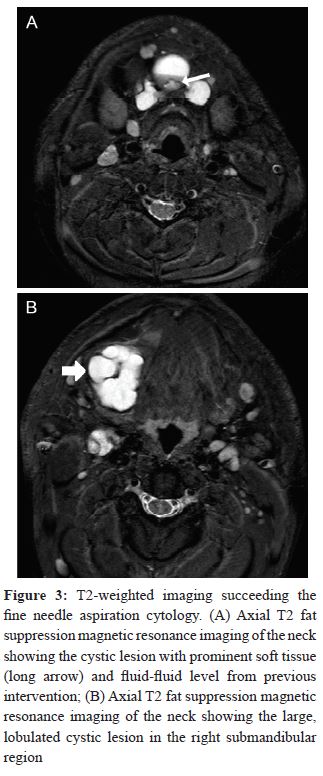

Another lesion was identified in the right submandibular area anterior to the right submandibular gland, which was displaced posteriorly due to mass effect from the lesion. Multiple enlarged cervical lymph nodes were noted, some of which showed central necrosis and calcifications. FNAC of the neck mass revealed papillary carcinoma. A pre- and post-gadolinium contrast enhanced MRI of the neck was subsequently performed for local staging and toassess the extension of the carcinoma. It revealed anirregular, lobulated predominantly cystic lesion in the midline neck at the hyoid bone level anteriorly. The lesion was predominantly hyperintense ofT2-weighted images showing a distinct fluid level consistent with hemorrhage due to the preceding FNAC (Figure 3).